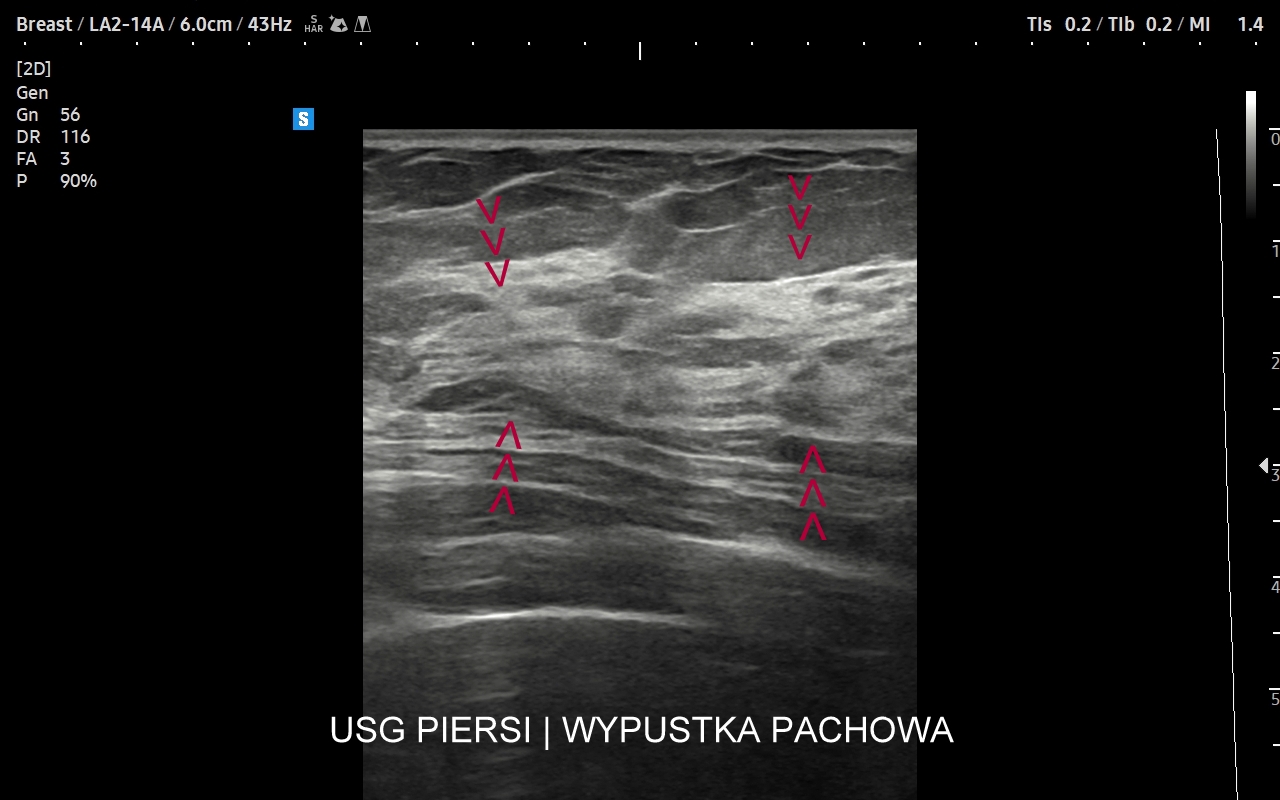

Badanie USG piersi jest podstawową i jedną z najważniejszych metod obrazowania gruczołu piersiowego. Wskazania do jego wykonania obejmują profilaktykę raka gruczołu piersiowego u kobiet oraz wskazania diagnostyczne. Profilaktyczne badanie USG piersi u kobiet wykonywane powinno być regularne raz w roku już nawet od 25 roku życia, w szczególności w przypadku rodzinnego obciążenia onkologicznego. Ze wskazań diagnostycznych badanie USG gruczołu piersiowego przeprowadzane jest w wypadku pojawienia się macalnego guzka piersi, deformacji piersi, jej stwardnienia i bolesności, stanu zapalnego, wycieku z brodawki sutkowej, czy powiększenia się pachowego węzła chłonnego. USG gruczołu sutkowego bywa również uzupełnieniem badania mamograficznego.

USG piersi z implantami

Badanie USG piersi z implantami jest szczególną procedurą diagnostyczną. Przeprowadza się ze wskazań wcześniej opisanych, jak w przypadku piersi bez implantów, ale także w schorzeniach ściśle związanych z implantem. Przykładami są powikłania chirurgiczne takie jak przemieszczenie się implantu, krwiak, ropne zapalenie tkanek wokół implantu, jego pęknięcie, a także wystąpienie chłoniaka BIA-ALCL (ang. breast implant associated anaplastic large cell lymphoma) jako odległego powikłania wszczepienia implantu piersi.